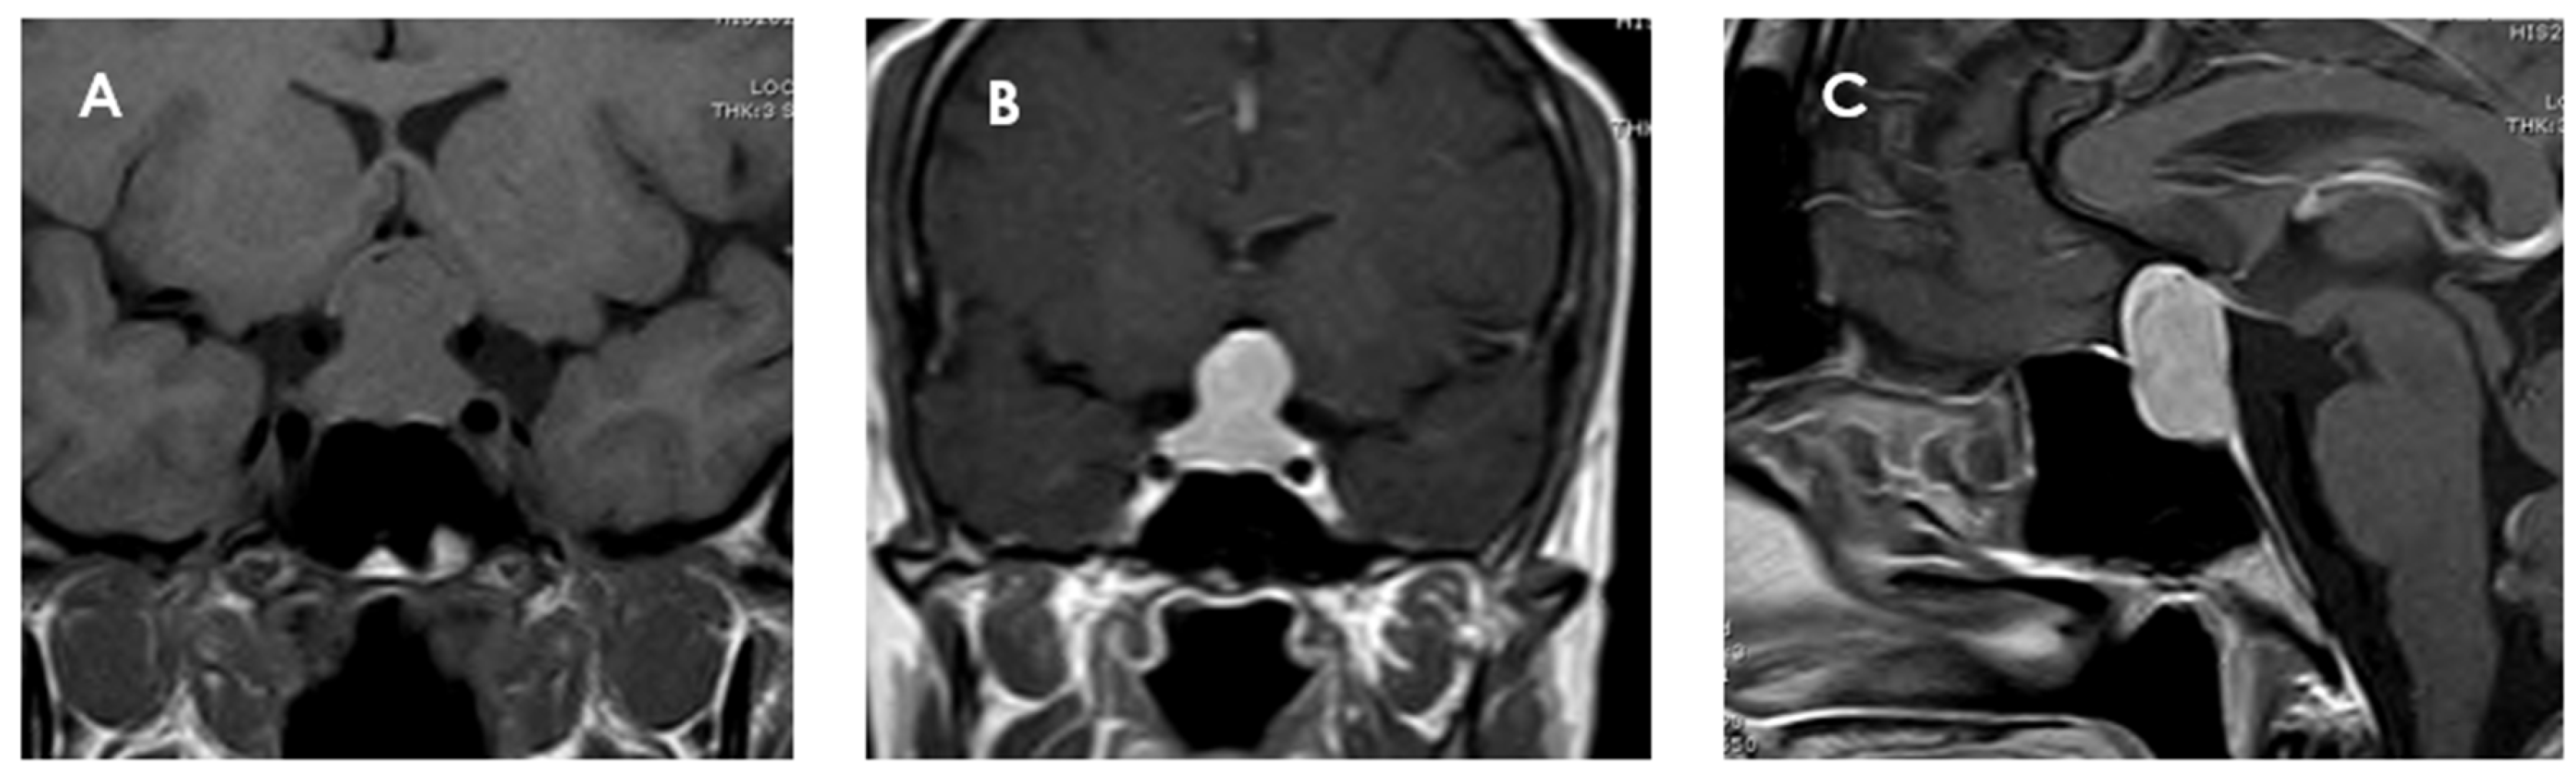

Figure 3. Magnetic resonance imaging of a pituicytoma (PTC). The lesion measures 25 × 12 × 14 mm (cranial–caudal × anteroposterior × transverse), with superior displacement of the optic chiasm and discrete compression of the pituitary stalk. (A) Coronal T1 sequence without contrast showing an isointense mass located in the sellar and suprasellar region. (B) Coronal T1-weighted coronal section with gadolinium showing homogeneous enhancement of the lesion. (C) Sagittal T1-weighted contrast-enhanced sagittal section confirming the suprasellar location of the mass, well delimited and with intense contrast uptake, and with no signs of invasion to adjacent structures.